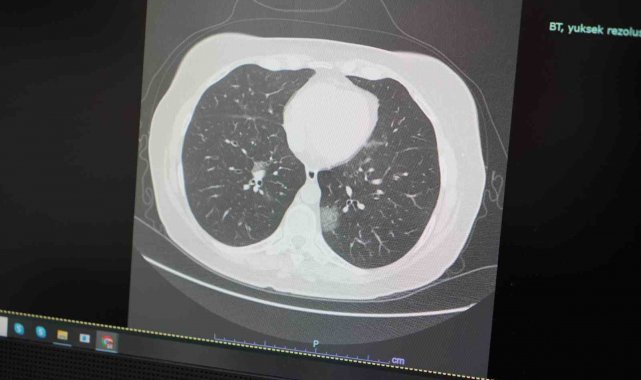

Göğüs Hastalıkları Uzmanı Prof. Dr. Şevket Özkaya, Mayıs ayında artan sıcaklıklar ve çevresel faktörlerle birlikte hem alerjik hem de viral hastalıkların yaygınlaştığını belirterek, özellikle alerjik astım ve rinit gibi rahatsızlıkların belirtilerinin Covid-19 gibi viral enfeksiyonlarla karışabileceğine dikkat çekti.

Mayıs ayıyla birlikte doğada yoğunlaşan polenlerin, alerjik bünyeye sahip kişilerde ciddi solunum yolu problemlerine yol açabileceğini ifade eden Prof. Dr. Özkaya, "Havaların ısınması ile birlikte insan hareketliliği artıyor. Bu da viral enfeksiyonların yayılımını hızlandırıyor. Aynı zamanda alerjenlerin de etkisiyle hastalarda nefes darlığı, öksürük, burun akıntısı gibi semptomlar görülüyor. Covid-19'un da benzer belirtiler göstermesi, tanı konulmasını zorlaştırabiliyor" dedi.

Göğüs Hastalıkları Uzmanı Prof. Dr. Şevket Özkaya, küresel iklim değişikliklerinin sağlık üzerindeki etkilerine dikkat çekerek, özellikle bahar aylarında alerjik ve viral hastalıklarda büyük artış yaşandığını söyledi. Mevsimlerin sürelerinin kısalmasıyla ilkbaharın artık yalnızca Mayıs ayıyla sınırlı kaldığını belirten Özkaya, "Mayıs ayına artık tek başına ilkbahar ayı diyebiliriz. Mayıs ayında havaların ısınmaya başlaması ile alerjik astım ve alerjik rinit başta olmak üzere hem alerjik hastalıklar hem de insan hareketliliğinin artması ile viral hastalıklar zirve yapacağını biliyoruz. Mevsimlerin ve iklimlerin birbirine hızlı karışması ile çevresel değişikliklerden etkilenen hastalıkların da birbirine karışıyor. Mevsimlerin geçiş dönemleri olan ilkbahar ve sonbahar mevsimleri hızla kısalıyor. Yıl boyu sıcak ve serin dönem yaşanacak. Bunun arasında geçişler ani olduğu için sert rüzgarlar, yağmurlar ve afetlerle karşı karşıya kalıyoruz. Artık ilkbahar ve sonbahar mevsimleri 3 ay değil, günler içinde 4 mevsimi yaşatacak kadar kısaldı. Belki de daha sonra ortadan da kalkacak. Onun yanında soğuk bir kış ve sıcak bir yaz olacak" diye konuştu.

Hastalıklardaki belirti benzerliğine dikkat çeken Özkaya, "Alerjik rinit ve alerjik astım başta olmak üzere, havaların ısınması ile çiçek ve ağaç polenleri birden solunan havaya karışacak ve artmış, geçmeyen, uzun süren öksürük, burun ve boğaz rahatsızlıkları ile astım benzeri zatürre ve bronşit vakaları göreceğiz. Hastalarımız maalesef, geçmeyen, uzamış öksürük ve nefes darlığı şikâyetlerinin alerjik mi yoksa viral bir başka bir hastalık mı olduğunu anlayamıyor. Okulların açık olması ve ısınan hava ile özellikle çocuklarımız polen dolu bu dış ortamda daha fazla hareketli zaman geçirmeleri ve ani ısı değişikliklerinden çabuk etkilenmeleri nedeni ile hem alerjik şikayetlerinde hem de influenza, RSV, Adeno ve Covid virüsleri başta olmak üzere viral etkenlere daha fazla maruz kalacaklar. Bunun sonucu hem çocuklarımızda uzamış öksürük ve ateş şikayetleri olacak, hem de bu virüsleri evdeki büyüklere taşıyacaklar. Okullarda özellikle öğretmenlerimiz ve velilerimiz bu konuda uyanık olmalarını öneriyoruz. Ve artık mevsimlerin, iklimlerin birbirine karışması ile çevresel değişiklerden etkilenen hastalıklar da birbirine karışıyor. Öksürük, ateş ve nefes darlığı çeken ve düzelmesi geciken, iyileşmeyen her hastanın mutlaka göğüs hastalıkları uzmanına görünmeleri gerekiyor" şeklinde konuştu.